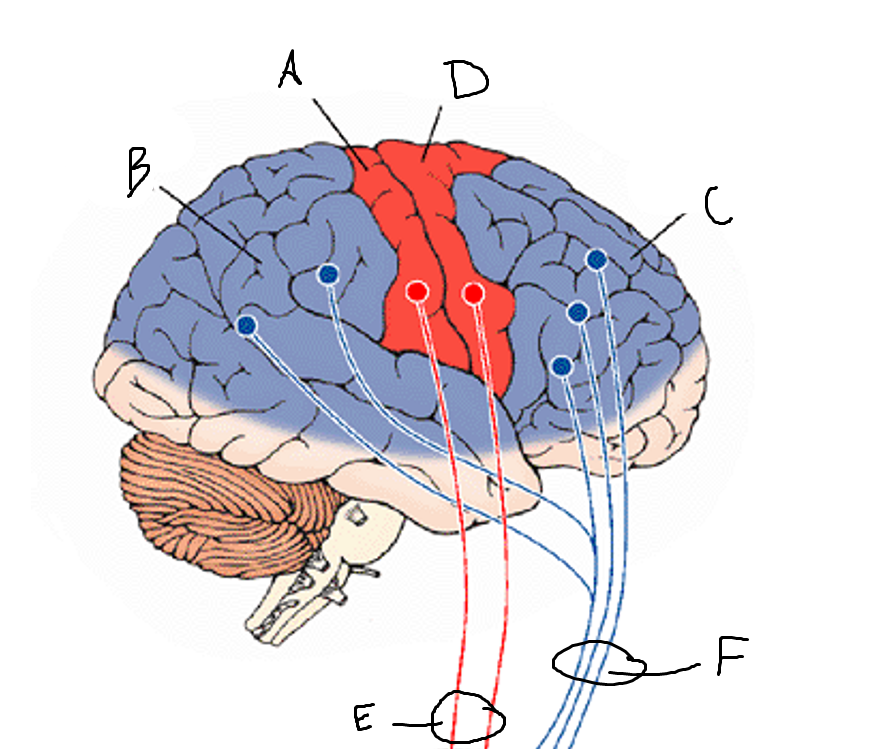

basal ganglia

A

somatosensory cortex

B

parietal association cortex

C

frontal and prefrontal cortices

D

primary motor cortex

E (where are the projections?)

putamen

F (where are the projections?)

caudate